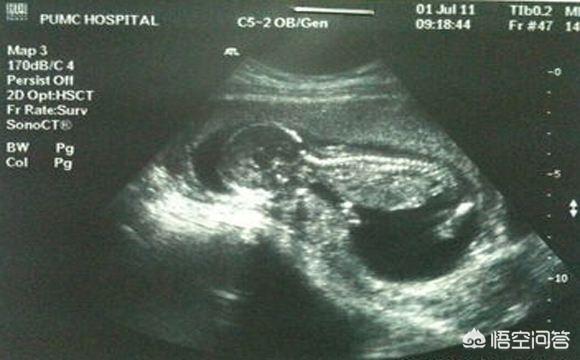

L'échographie B vérifie généralement le développement du fœtus et la position du placenta, et concerne rarement le problème des maladies fœtales. Seule l'échographie 4D permet de dépister les malformations fœtales. Votre question porte donc sur l'échographie 4D et non sur l'échographie B.

L'échographie 4D est une version améliorée de l'échographie b-scan, qui permet de détecter les malformations fœtales, les organes du visage et du corps du fœtus, les malformations des membres, telles que : fente labiale fœtale, syndactylie, quadruple cavité cardiaque, ectopie viscérale,...

Une échographie 4D pendant la grossesse permet de vérifier la présence de cardiopathies congénitales, d'hydrocéphalie, de fentes labiales et palatines, ainsi que le développement des membres du fœtus. L'échographie 4D permet également de voir l'image en mouvement du fœtus à l'intérieur du corps de la mère.

Communément appelé échographie 3D ou échographie 4D, il s'agit en fait d'un examen échographique visant à exclure la présence de maladies congénitales dans les différents systèmes et organes du fœtus.

L'échographie (échographie 4D) est un élément indispensable du test de grossesse. Elle est principalement chargée d'examiner la surface du corps du fœtus et divers organes pour y déceler des malformations. Par exemple : le cœur du fœtus, le cerveau, les reins et d'autres parties de la maladie.